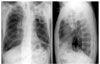

Lucite-ball plombage

Plombage refers to the placement of any inert object against the lung to collapse the underlying cavity. 1 Polymerized methyl methacrylate, or Lucite, balls-similar in size and form to Ping-Pong balls-were inserted into the chest to collapse the lung and to maintain adequate thoracic expansion.4-9 These spheres were supposed to be nonirritating to adjacent tissue, noncarcinogenic and nonantigenic, insoluble, slightly resistant to roentgen rays, round and easily fitted into any space, lightweight to prevent erosion or migration, and able to float (in case fluid developed). The assumption was that the spheres stimulated a thin, strong, dense, fibrous membrane that could prevent the spread of disease beyond its surface.7